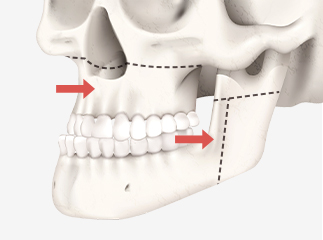

양악수술은 상악(윗턱)과 하악(아래턱)을

동시에 교정해 턱뼈 성장 이상, 부정교합,

턱관절 장애 등을 바로잡고

기능을 개선하는 수술입니다.

상악과 하악을 절골합니다.

절골된 상악과 하악을

수술 계획에 맞게 이동하여

교합을 맞춥니다.